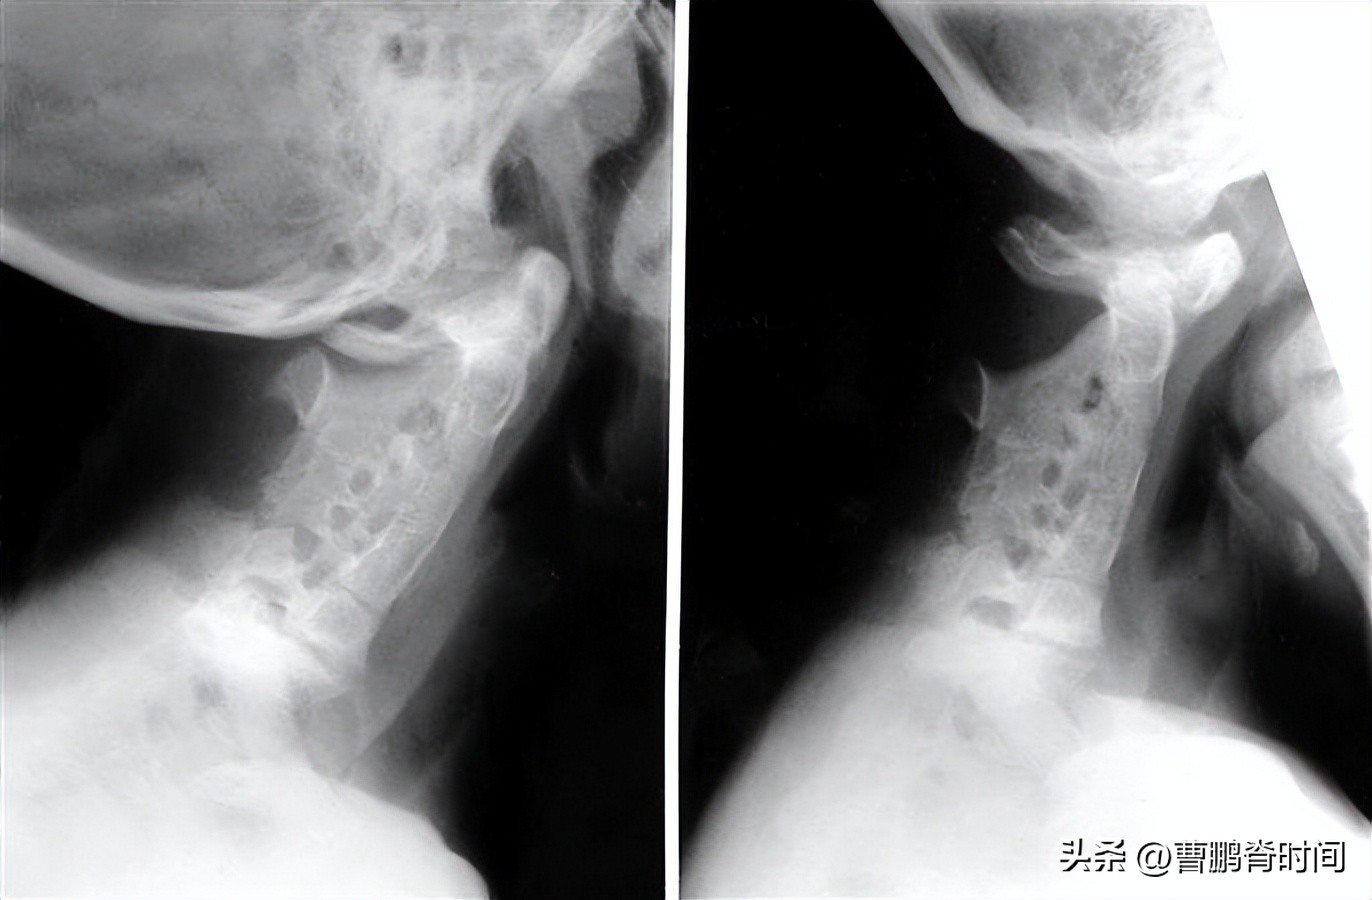

如果同时含有 短颈 、 后发际线较低 和 颈部活动受限 的“三联征”表现,就应该提高警惕。

请及时前往医院通过完善颈椎X线片的检查,必要时进行颈椎CT、颈椎MRI、基因检测等相关检查,以明确诊断和评估病情。